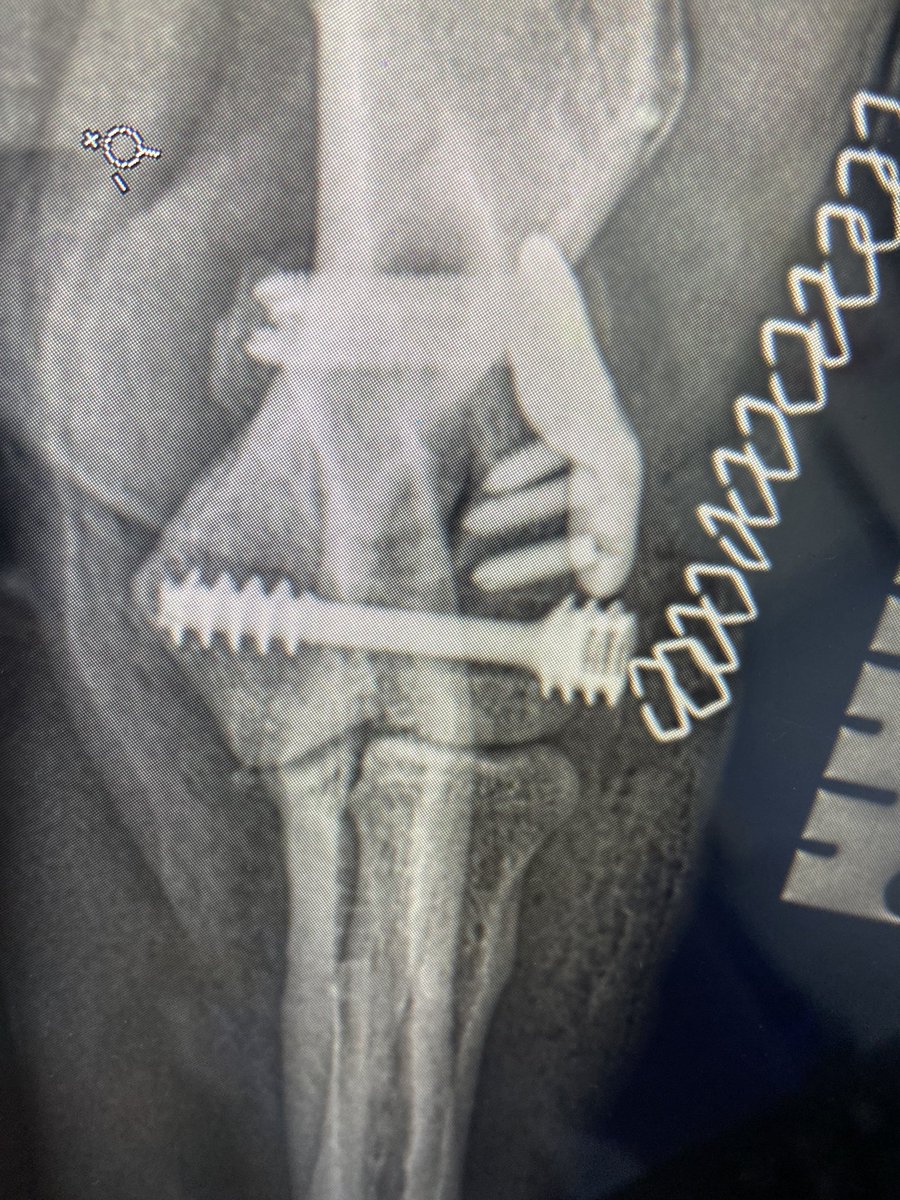

3D-printed drill guide from @FusionImplants making placing HIRS screw for canine humeral intracondylar fissure super-easy and predictable #progress @ESS_Health